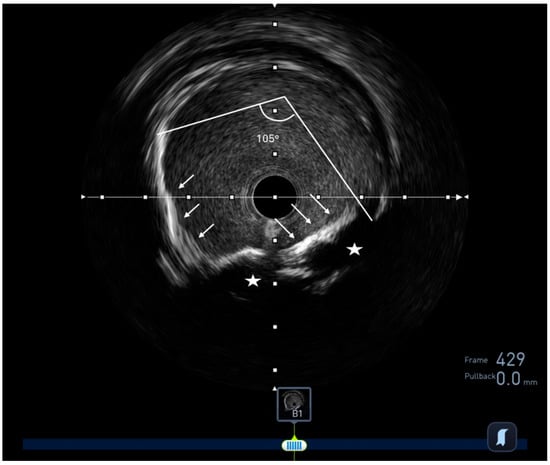

2.1. Intravascular Ultrasound (IVUS)